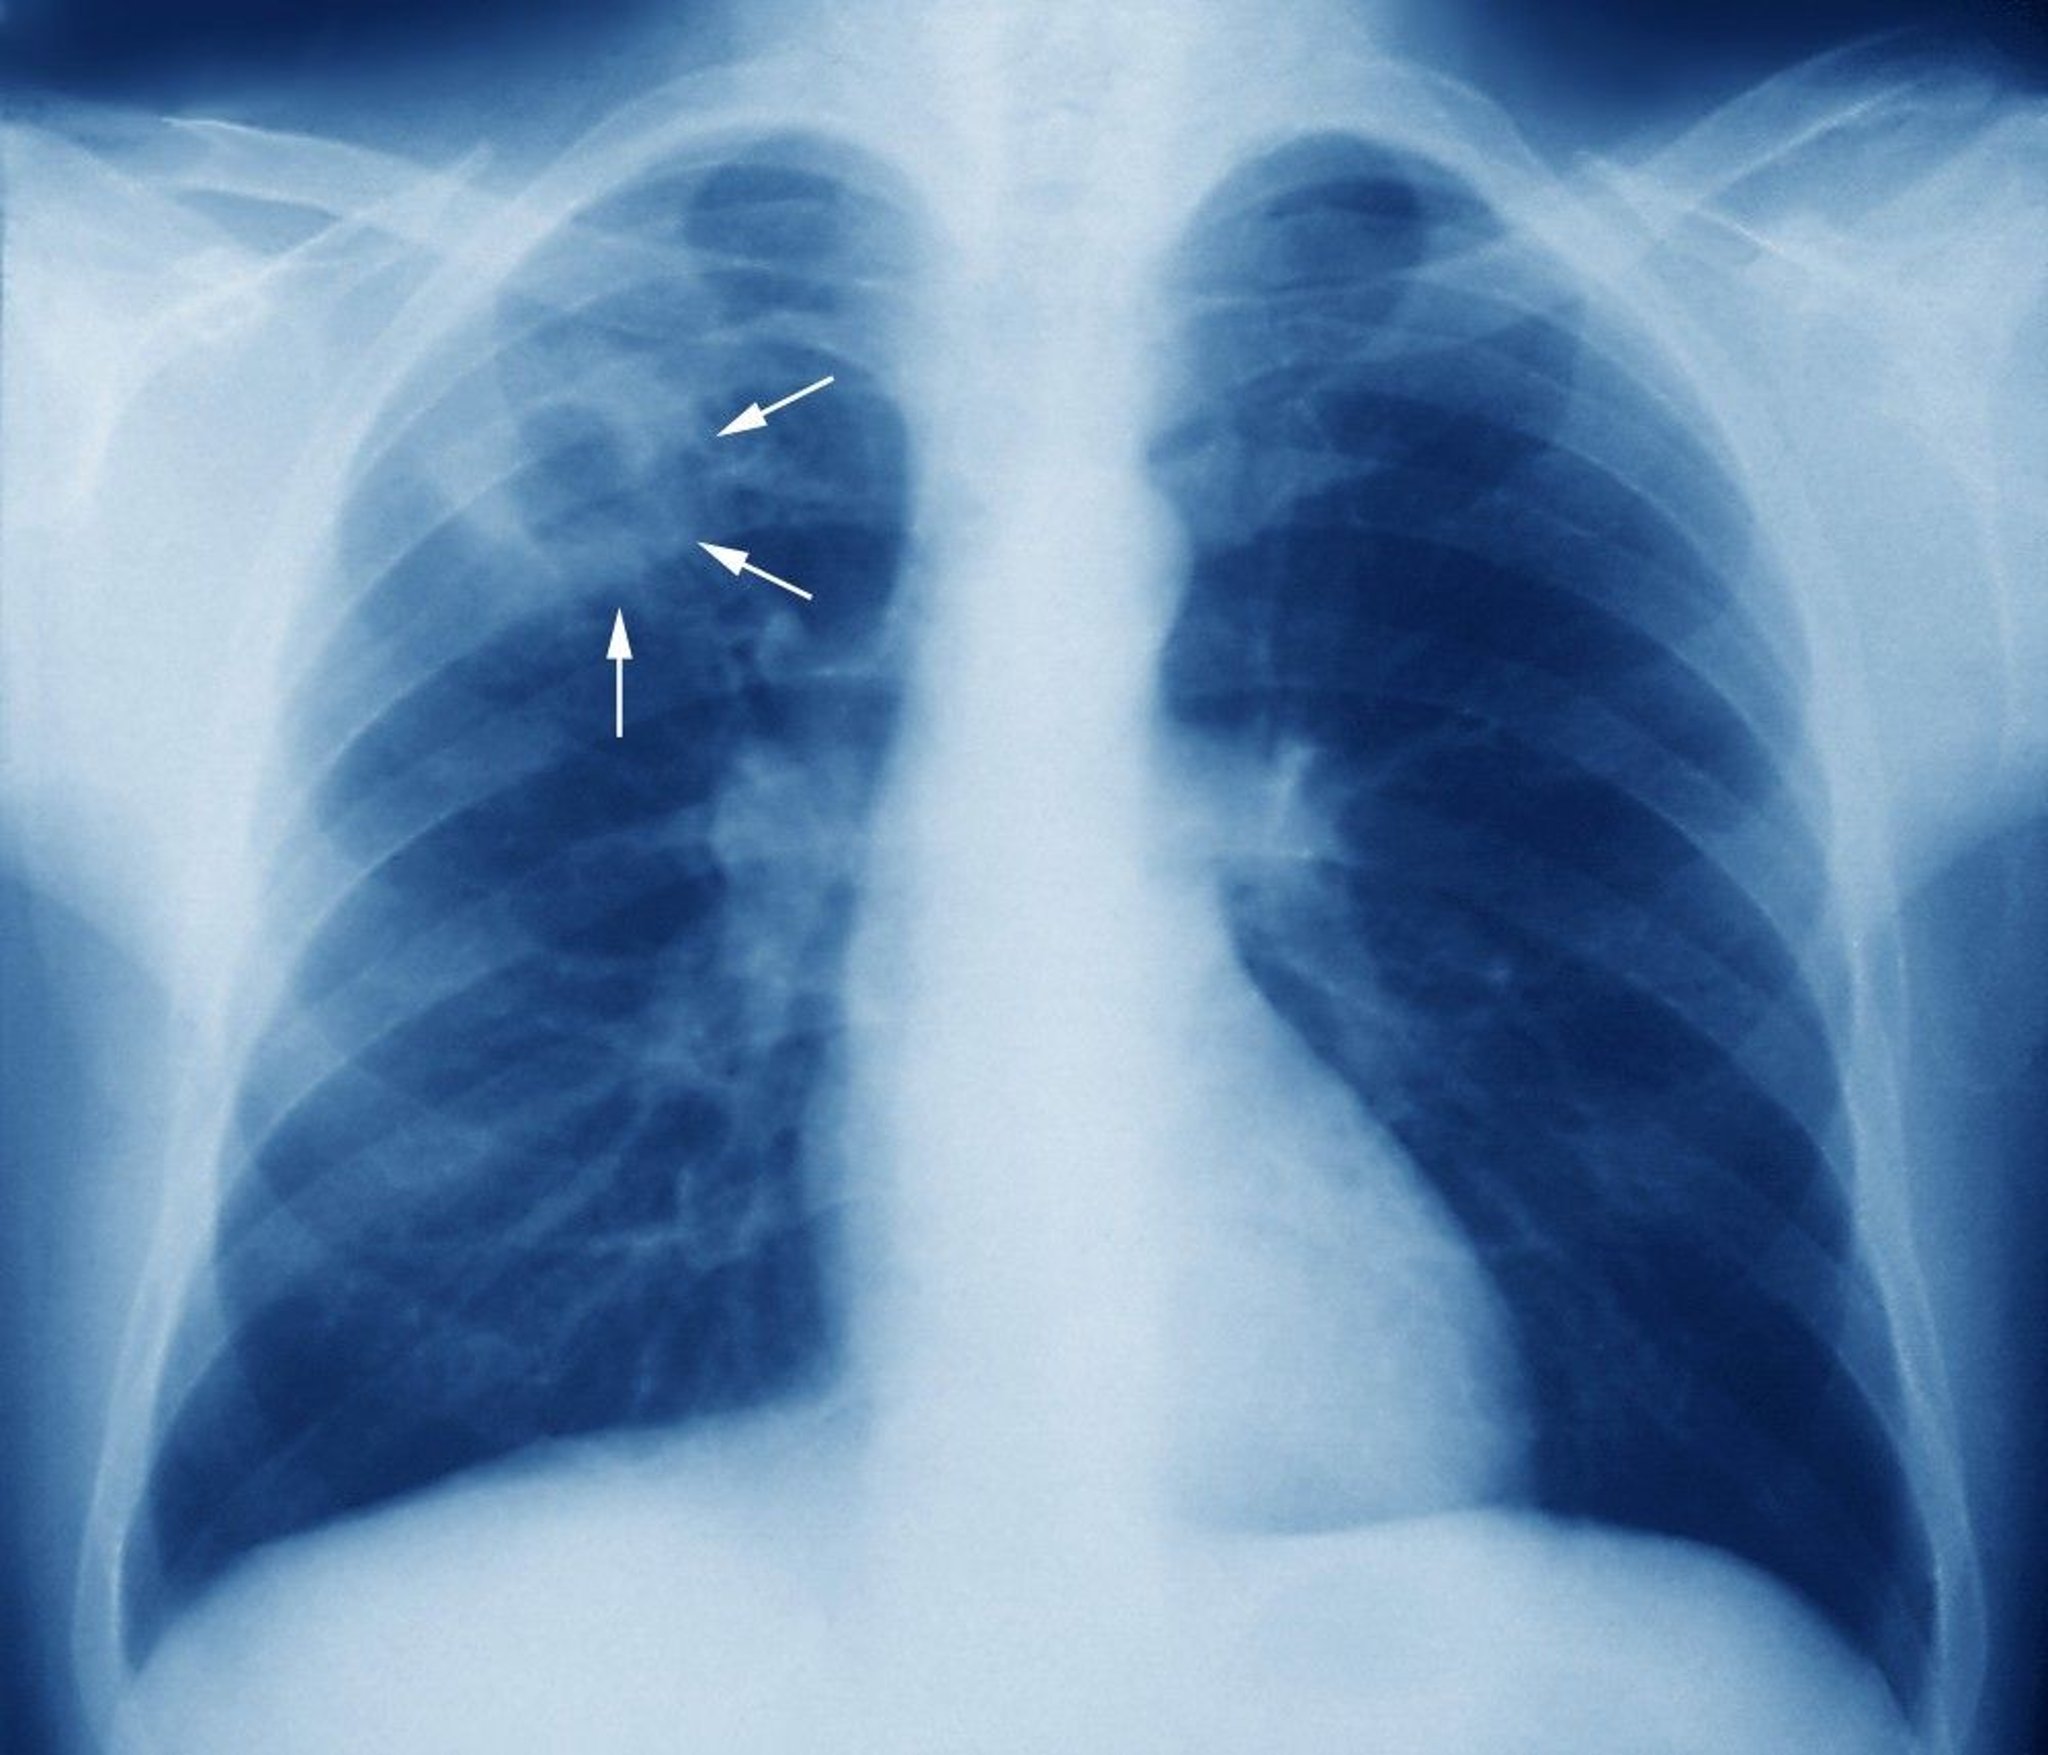

A right upper lobe cavitary lesion on a chest x-ray of a patient with tuberculosis.

ZEPHYR/SCIENCE PHOTO LIBRARY